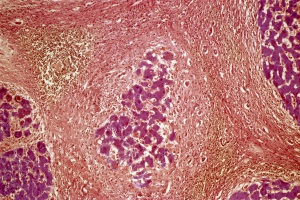

Цирроз печени – тяжелое хроническое заболевание, при котором функциональные клетки печени (гепатоциты) постепенно замещаются соединительной тканью, что приводит к уменьшению их общего количества.

К сожалению, в последнее время в гастроэнтерологической практике достаточно часто встречаются пациенты с фиброзом и циррозом печени.

Нецирротический фиброз печени (первичный гепатопортальный склероз) известен также под названиями идиопатическая портальная гипертензия, или нецирротический портальный фиброз.